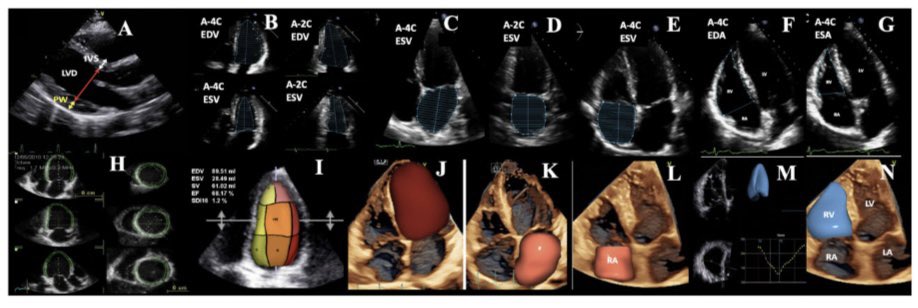

The first day of our highly anticipated Multimodality Imaging Techniques Meeting which brought together a distinguished group of experts and attendees eager to deepen their knowledge in cardiovascular imaging. #MMIT #MultimodalityImaging #CardiovascularImaging #echo #TEE #TTE

#MMIT #MultimodalityImaging #CardiovascularImaging #echo #TEE #TTE